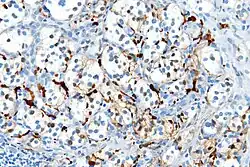

Varios miembros de la familia de proteínas S100 son útiles como marcadores para determinados tumores. Pueden ser encontradas en melanomas, en el 100% de schwannomas, 100% de neurofibromas (de forma más débil que en los schwannomas), 50% de los tumores malignos de la vaina de nervios periféricos (de forma débil y/o focal), histiocytoma y célula clara sarcomas.[8] Además, las proteínas S100 son marcadores de enfermedades inflamatorias. También puede mediar en la inflamación y actuar como antimicrobianos.[9]